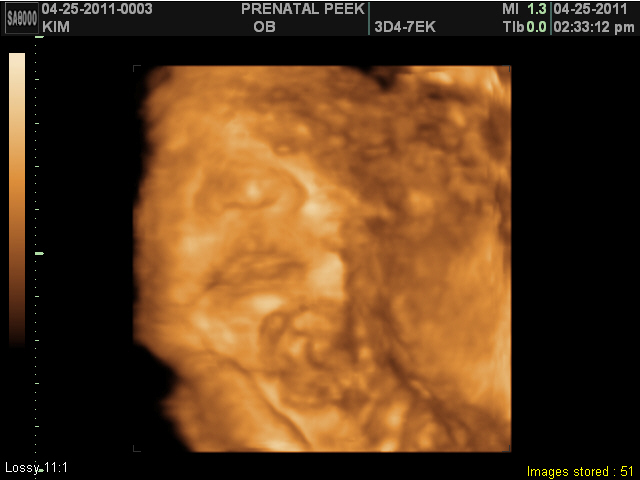

Prenatal Peak Round 2